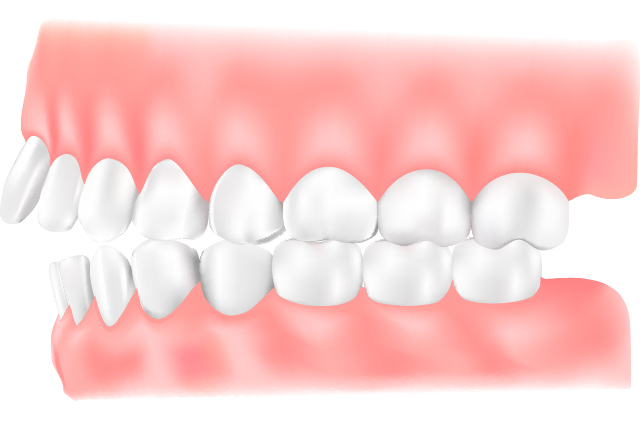

出っ歯(上顎前突:じょうがくぜんとつ)

上顎の前歯が前に傾斜していたり、歯が前に突き出していたりする状態で、一般的に「出っ歯」と呼ばれています。見た目の問題や発音障害が生じるほか、口をしっかり閉じられないことで、口呼吸が習慣となり、口腔内の乾燥によりむし歯や口臭が起こりやすくなります。また、顔のけがで前歯を折ったり、唇を切ったりしやすくなります。噛み合わせにより、下の前歯が上の前歯の裏側の歯ぐきを傷つけてしまうこともあります。